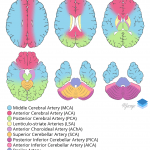

- Left ACA territory infarct

- ACA territory infarcts are less common than MCA or PCA territory infarcts

- While ACA infarcts are most often embolic, severe midline shift with subfalcine herniation can compress the ACAs leading to ischemia